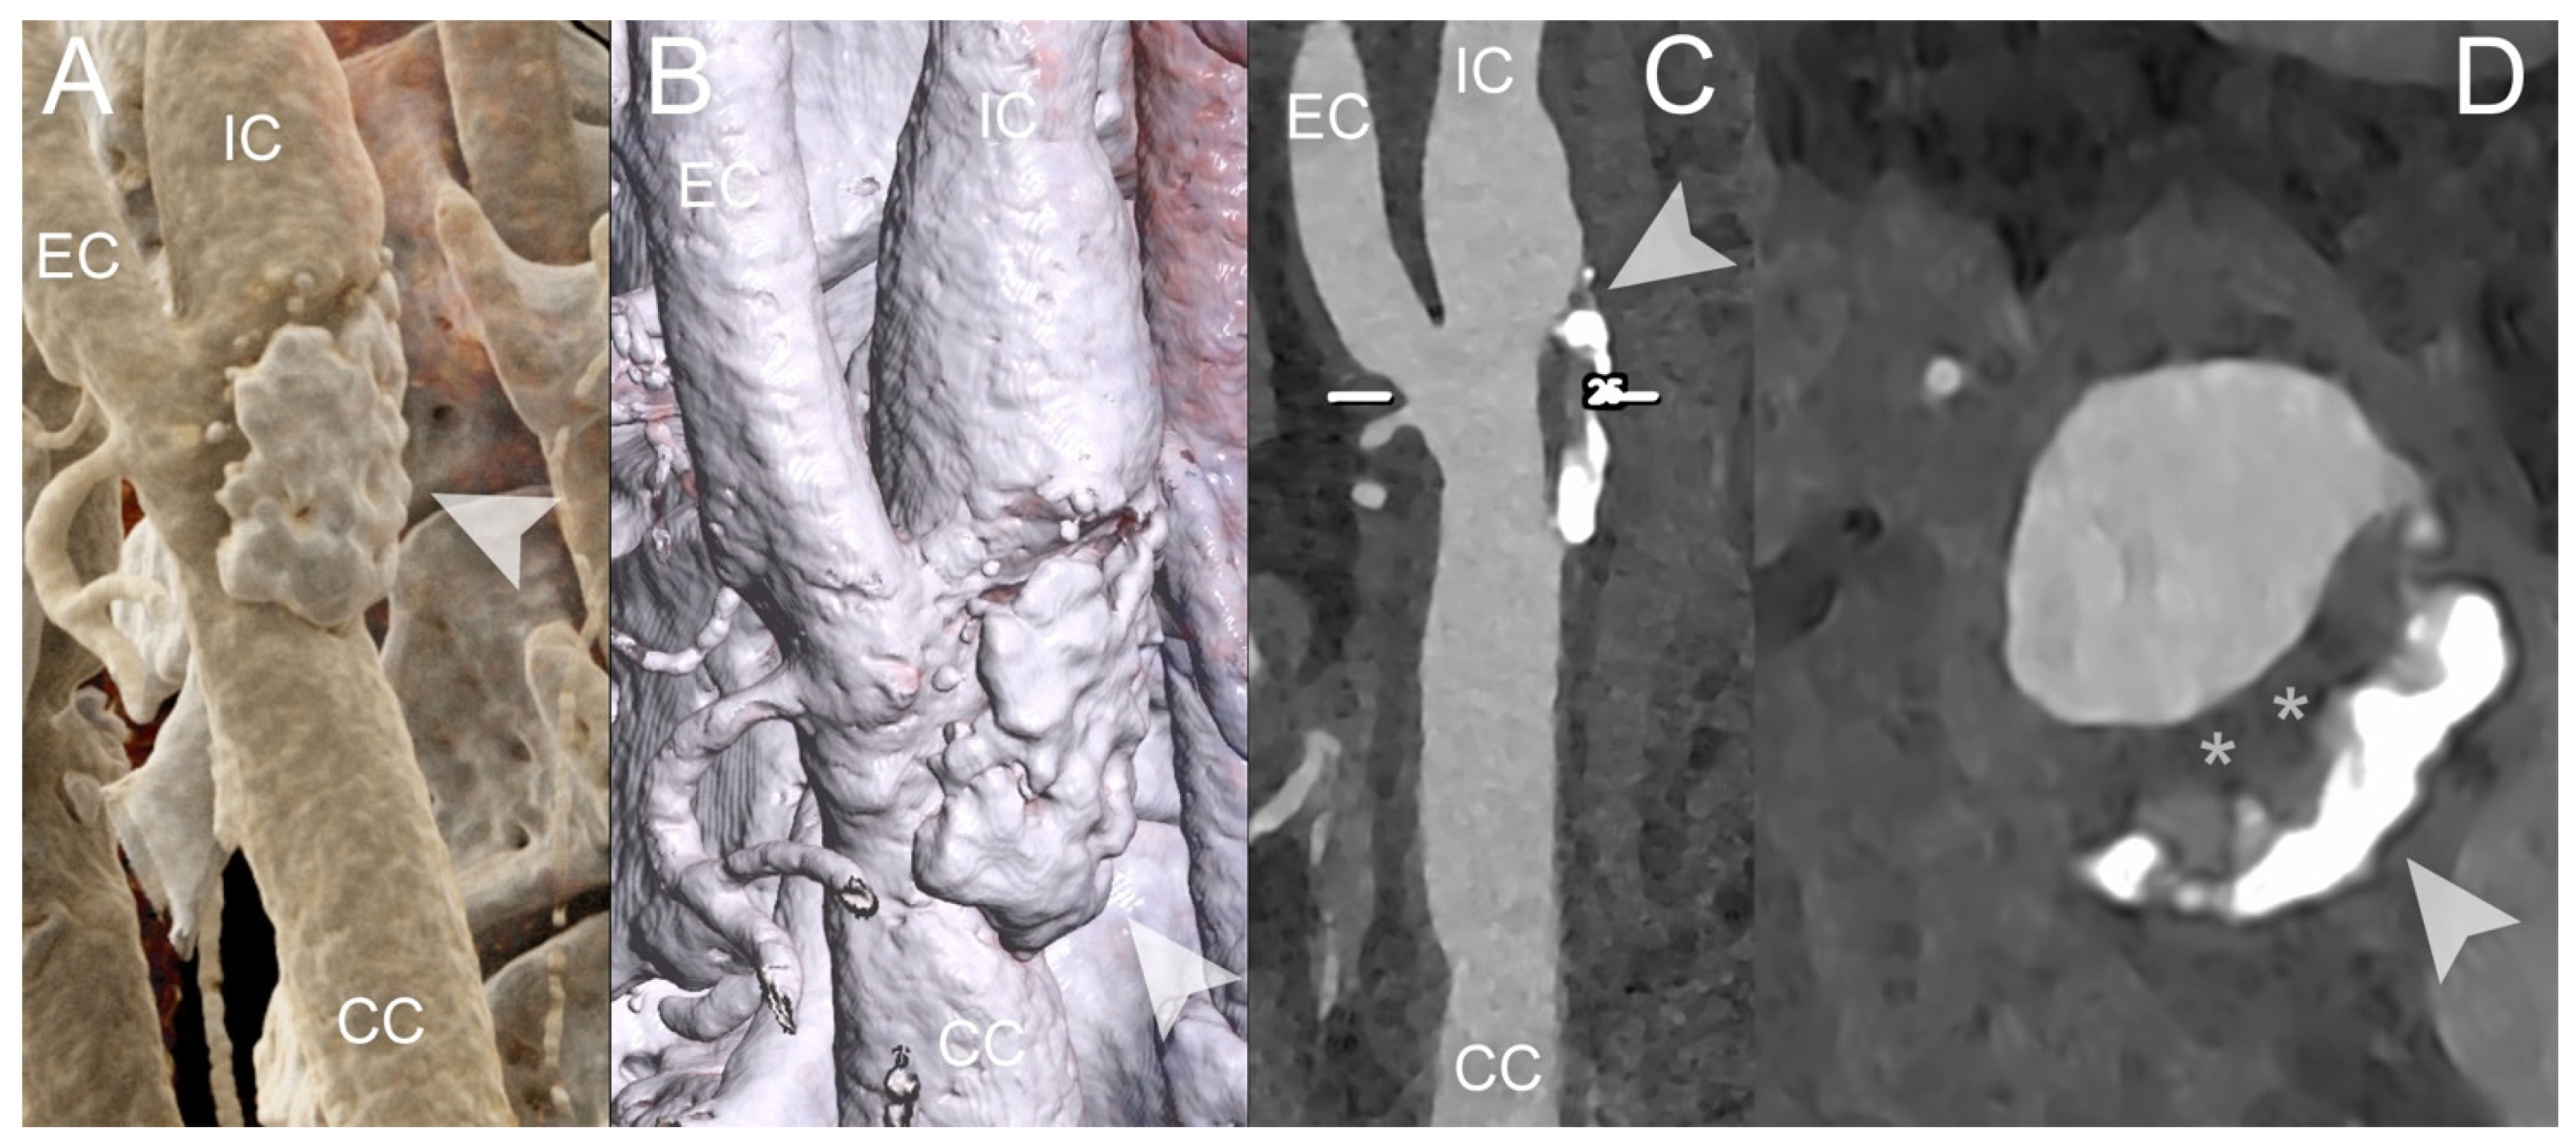

4. Clinical Application of PCCT in Carotid Plaque

- Dahal, S.; Raja, A.Y.; Searle, E.; Colgan, F.E.; Crighton, J.S.; Roake, J.; Saba, L.; Gieseg, S.; Butler, A.P.H. Components of carotid atherosclerotic plaque in spectral photon-counting CT with histopathologic comparison. Eur. Radiol. 2023, 33, 1612–1619. [Google Scholar] [CrossRef]

- Shami, A.; Sun, J.; Gialeli, C.; Markstad, H.; Edsfeldt, A.; Aurumskjöld, M.-L.; Gonçalves, I. Atherosclerotic plaque features relevant to rupture-risk detected by clinical photon-counting CT ex vivo: A proof-of-concept study. Eur. Radiol. Exp. 2024, 8, 14. [Google Scholar] [CrossRef] [PubMed]

- Healy, J.; Searle, E.; Panta, R.K.; Chernoglazov, A.; Roake, J.; Butler, P.; Butler, A.; Gieseg, S.P.; Adebileje, S.A.; Alexander, S.D.; et al. Ex-vivo atherosclerotic plaque characterization using spectral photon-counting CT: Comparing material quantification to histology. Atherosclerosis 2023, 378, 117160. [Google Scholar] [CrossRef]

- Zainon, R.; Ronaldson, J.P.; Janmale, T.; Scott, N.J.; Buckenham, T.M.; Butler, A.P.H.; Butler, P.H.; Doesburg, R.M.; Gieseg, S.P.; Roake, J.A.; et al. Spectral CT of carotid atherosclerotic plaque: Comparison with histology. Eur. Radiol. 2012, 22, 2581–2588. [Google Scholar] [CrossRef] [PubMed]

- Marsh, J.J.; Rajendran, K.; Tao, S.; Vercnocke, A.; Anderson, J.; Leng, S.; Ritman, E.; McCollough, C. A Blooming correction technique for improved vasa vasorum detection using an ultra-high-resolution photon-counting detector CT. In Medical Imaging 2020: Physics of Medical Imaging; SPIE: Bellingham, DC, USA, 2020; Volume 11312. [Google Scholar] [CrossRef]

- Rajendran, K.; Leng, S.; Jorgensen, S.M.; Abdurakhimova, D.; Ritman, E.L.; McCollough, C.H. Detection of increased vasa vasorum in artery walls: Improving CT number accuracy using image deconvolution. In Medical Imaging 2017: Physics of Medical Imaging; SPIE: Bellingham, DC, USA, 2017; Volume 10132. [Google Scholar] [CrossRef]

- Marsh, J.F.J.; Vercnocke, A.J.; Rajendran, K.; Tao, S.; Anderson, J.L.; Ritman, E.L.; Leng, S.; McCollough, C.H. Measurement of enhanced vasa vasorum density in a porcine carotid model using photon counting detector CT. J. Med. Imaging 2023, 10, 16001. [Google Scholar] [CrossRef]